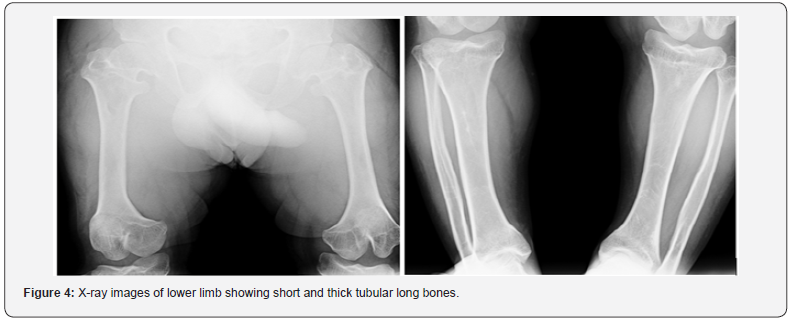

Achondroplasia is the most frequent form of short - limb dwarfism [1]. The phenotype is characterized by rhizomelic disproportionate short stature, enlarged head, midface hypoplasia, short hands and lordotic lumbar spine [2,3]. Its incidence is 1 in 10,000 to 1 in 30,000 [1]. Here we describe a case of achondroplasia in a 37-year-old male, who presented to endocrinology OPD for short stature. General physical examination showed large head, depressed nasal bridge short stature, with rhizomelic shortening of the arms and legs and normal trunk length (Figure 1). Patient had short, stubby fingers and excessive spacing between third and fourth finger (Figure 2). Anthropometry revealed a height of 115.5 cm (midparental height - 155.2 cm), weight of 41.4 kg. His vital signs were within the normal limits. Systemic examination did not reveal any abnormality. Hand‑wrist radiograph showed short metacarpal and phalanges with trident hand configuration (Figure 3). X ray of lower limb reveled short and thick tubular long bones (Figure 4). Based on clinical examination and radiological features; diagnosis of achondroplasia was confirmed.